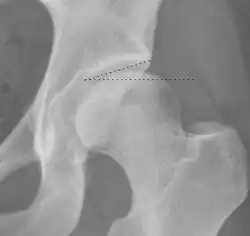

| Crossing ratio |

|

Percentage of acetabular walls crossing. Normal acetabulum is oriented in anteversion. Its value ranges from 15 to 20° in the equatorial plane of the acetabulum and decreases gradually towards the acetabular roof, where normal values range from 0 to 5°. Retroversion of the upper part of the acetabulum has been related with pincer type impingement. In radiography the presence of a "crossover sign" is produced when the posterior wall of the acetabulum crosses the anterior wall before reaching the acetabular roof. It is a sign of acetabular retroversion and it has been linked with overcoverage and pincer impingement. Nevertheless, this sign has been described in 6% of the normal population. Therefore, more important than its presence is the percentage of crossing. | <20%